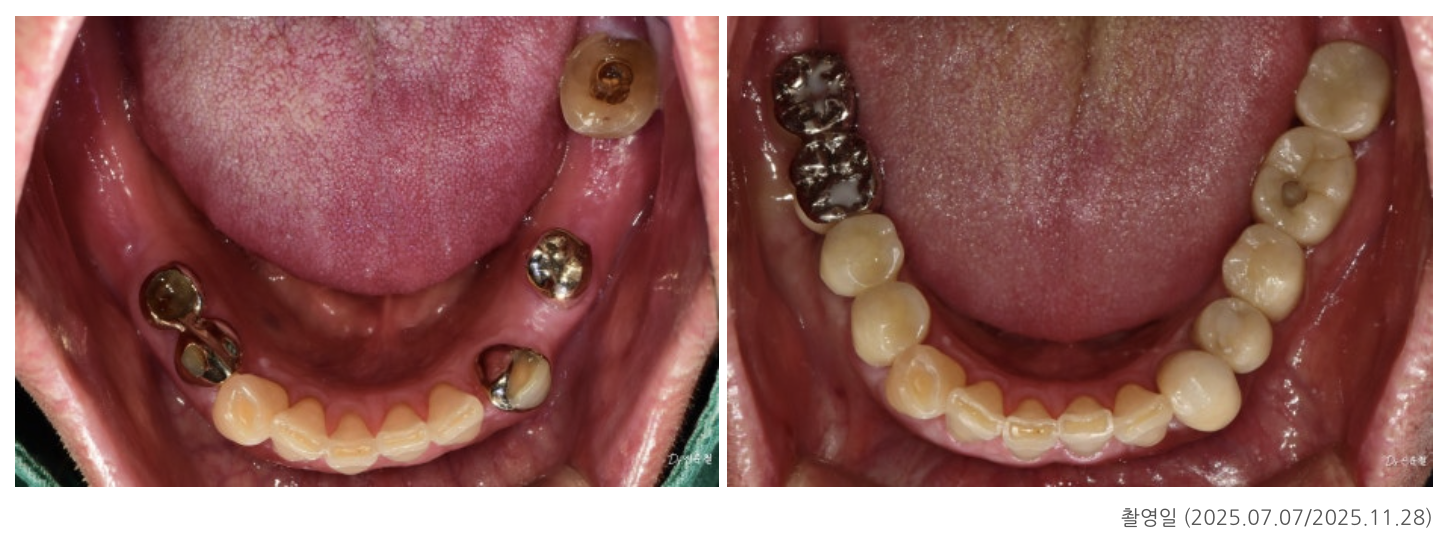

최종 결과: 전체 균형을 다시 회복

임플란트와 보철 치료가 모두 자리 잡은 뒤

다시 촬영한 사진에서는

✓ 양쪽으로 균형 있게 씹을 수 있는 교합

✓ 앞니·어금니의 힘 분산 안정

✓ 정출·기울기 문제 해결

이 확인되었습니다.

이 환자분은 지금도

정기 점검을 통해 교합 균형을 유지하는 중입니다.